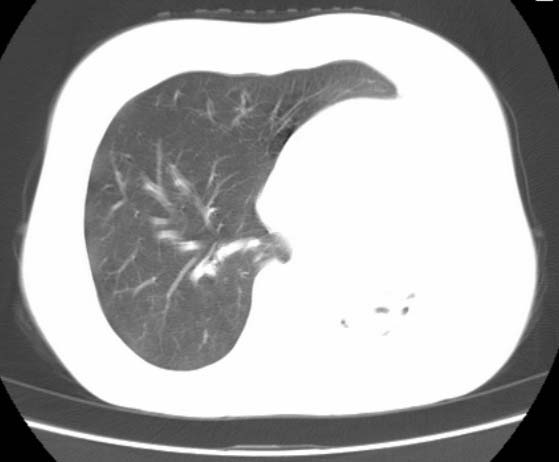

标题: CT25648:求教:是肺发育不全还是结核?

女  20岁。一月前咳血,诊“肺结核”抗痨治疗一月后,咳血停止,现复查。病人精神好。前后ct片对比未见明显变化。既往体检“正常”

1)考虑左肺结核并肺不张、支气管扩张。2)纵隔疝。

以前体检正常只能考虑左肺结核并肺不张、支气管扩张。2)纵隔疝。

考虑左肺结核,左肺毁损,纵膈左偏,既往体检正常不可靠,tb一个月也不会这个样子的,有钙化,应该病程较长,冰冻三尺非一日之寒!

左肺发育不全。